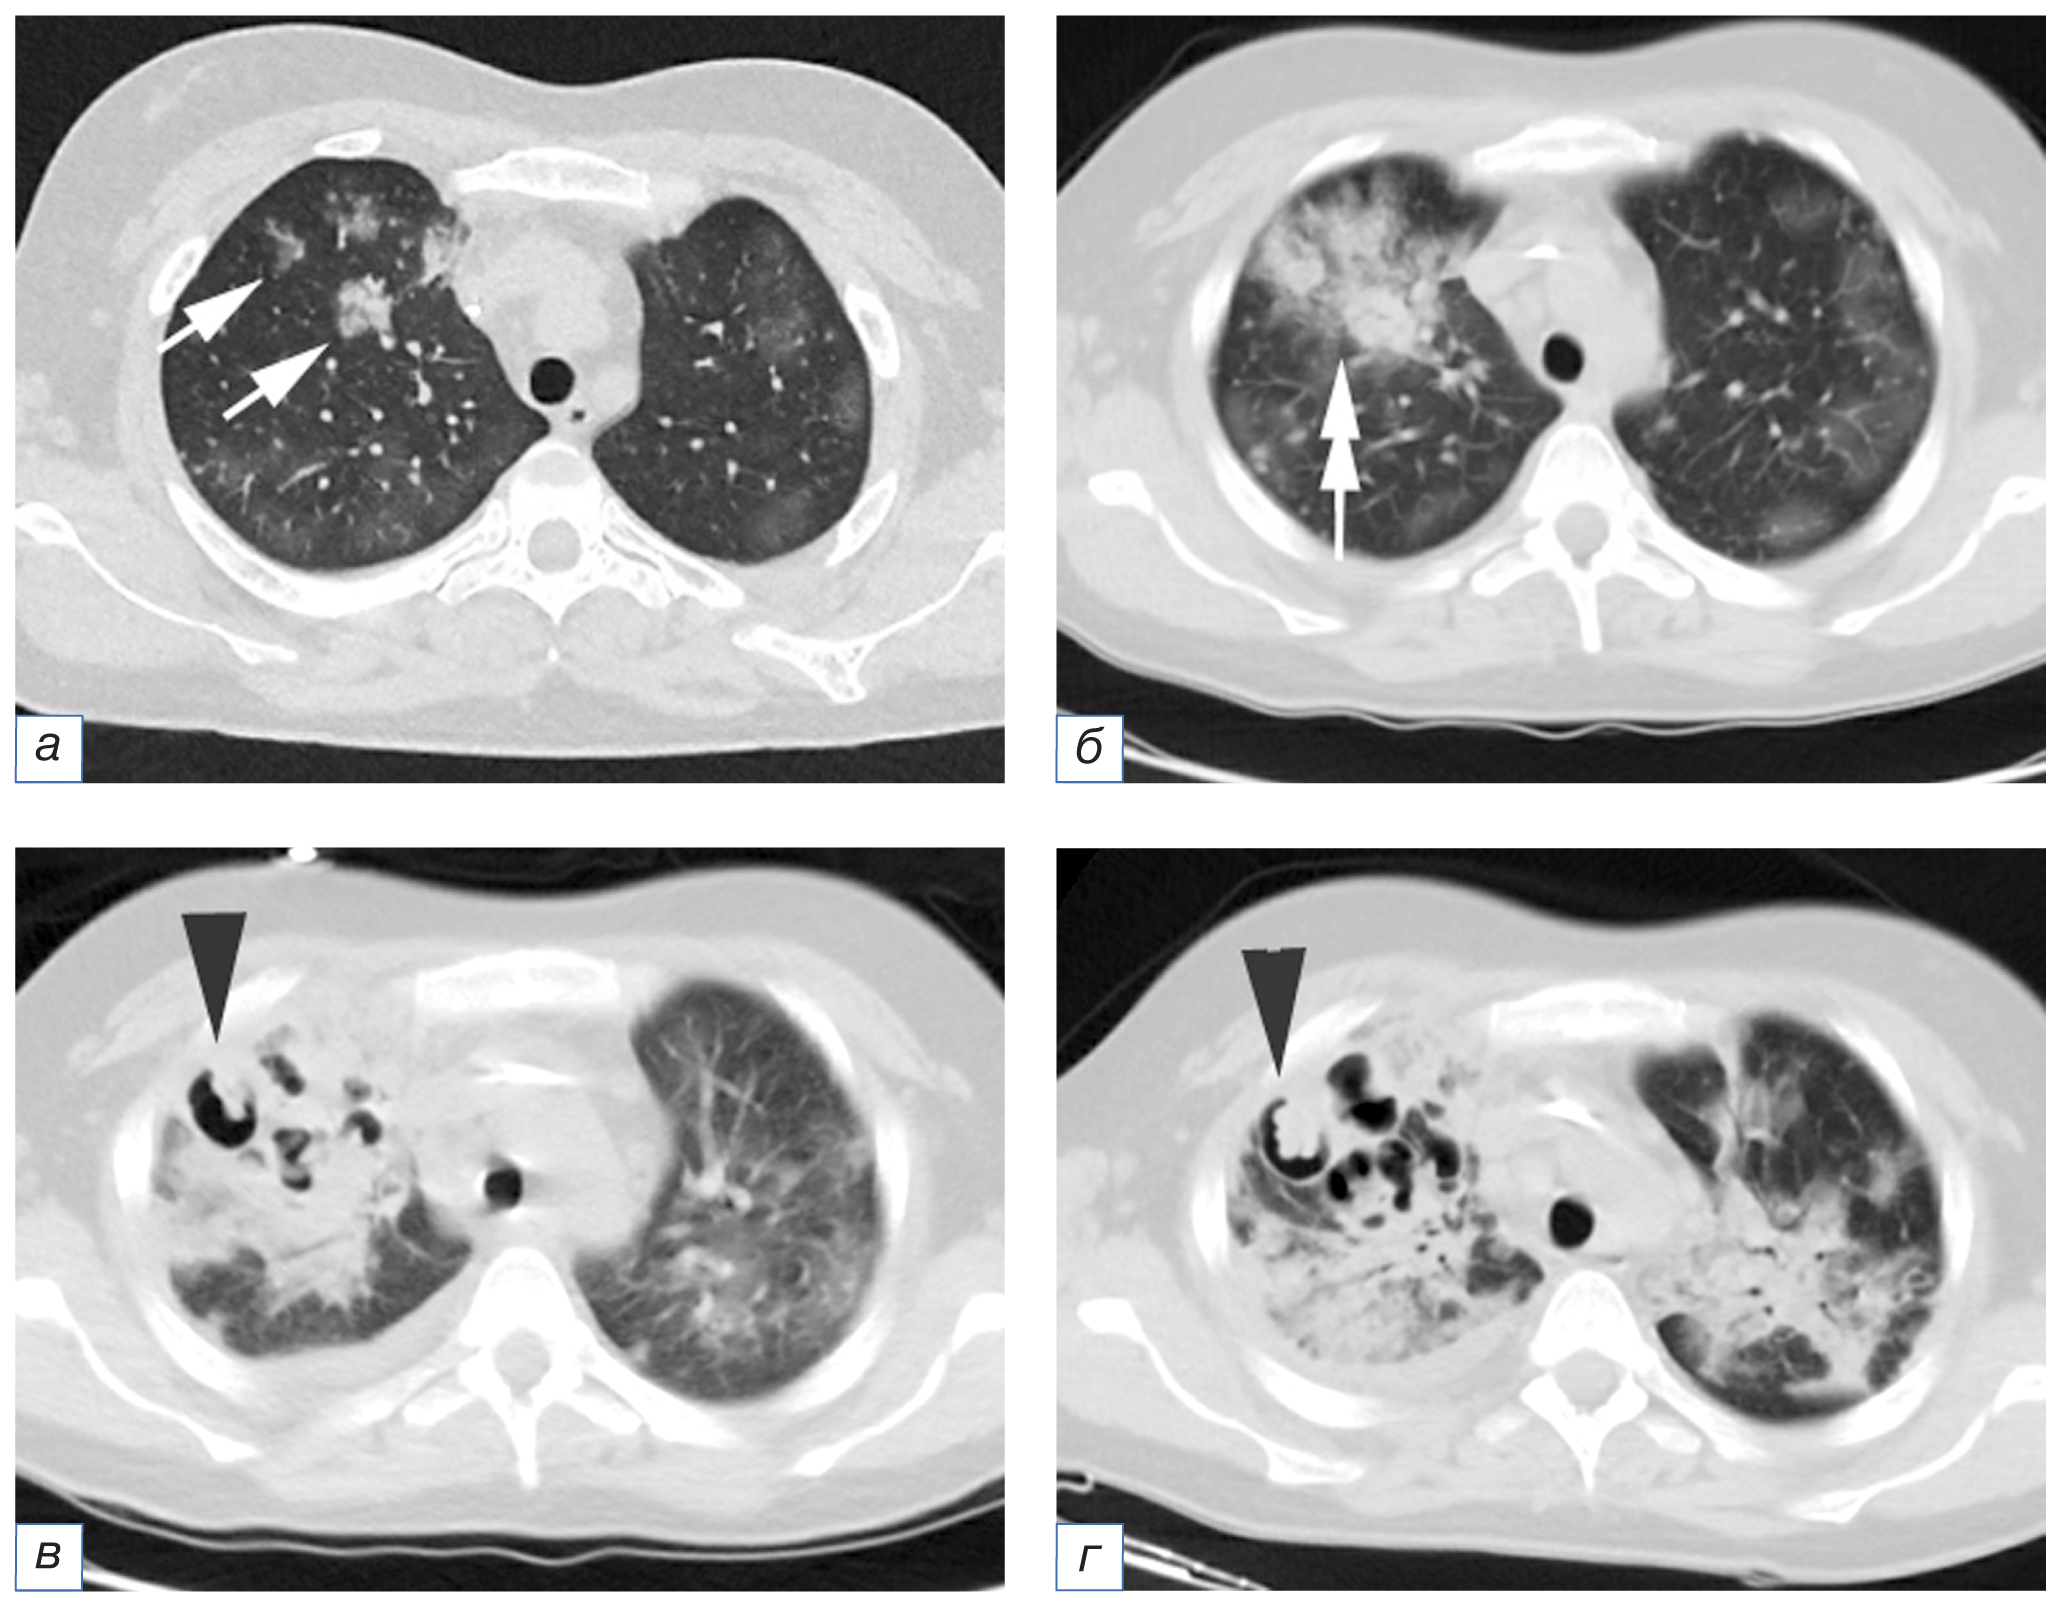

- ангиоинвазивный аспергиллёз: перибронховаскулярные уплотнения, одиночные и множественные очаги преобразуются в перибронхиальные консолидации (или их обнаруживают как первый самостоятельный признак) с последующей трансформацией в симптом «гнезда» и формированием полости или симптома «воздушный серп» (рис. 4);

Рис. 4. Пациент М., 69 лет, с аспергиллёзом лёгких, возникшем на фоне COVID-19 (COVID-АЛ): а — внутридольковые очаги, частично сливающиеся между собой (стрелки); б (через 6 дней) — трансформация очагов в перибронхиальные консолидации (двойная стрелка); в (через 9 дней) — формирование полостей на фоне консолидации (треугольная стрелка); г (через 15 дней) — увеличение размеров ранее выявленных и образование новых воздушных полостей, формирование симптома «воздушный полумесяц» (треугольная стрелка).

Fig. 4. Patient M., 69 years old, CAPA: а — intralobular foci partially merging with each other (arrows); б — 6 days after, the transformation of foci into peribronchial consolidations (double arrow); в — 9 days after, the formation of cavities against the background of consolidation (triangular arrow); г — 15 days after, an increase in the size of previously identified and the formation of new air cavities, the formation of the "air crescent" sign (triangular arrow).